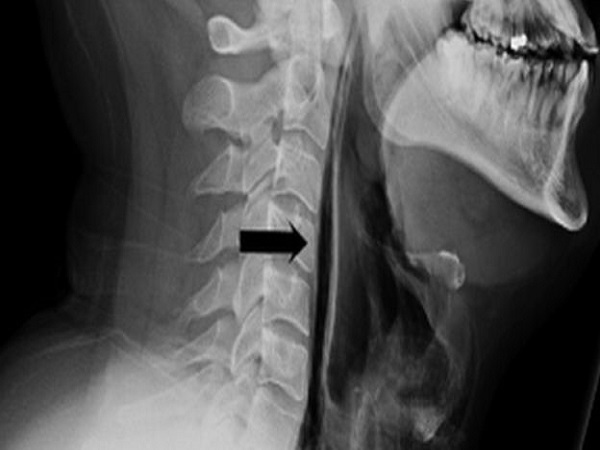

The doctors in Leicester have treated a 34-year-old man who has ruptured his throat while he was trying to control a high-force sneeze. Due to the high pressure of his sneeze, it ended up ripping through the soft tissue of the throat.

The force of the sneeze was so severe that it blew a hole in the back of his throat. It is reported that the man was barely able to speak or swallow after the sneeze. On the other hand, he even started hearing a popping and crackling sound as air passed through the new hole.

When medics examined the man, they found out that the crackling and popping sounds that he had complained of, extended from his neck and went down all the way to his rib cage. This was a sure sign of air bubbles finding their way into the deep tissue and muscles of the chest as the man did not visit the doctor initially.